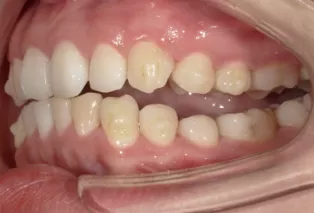

Intraoral photos